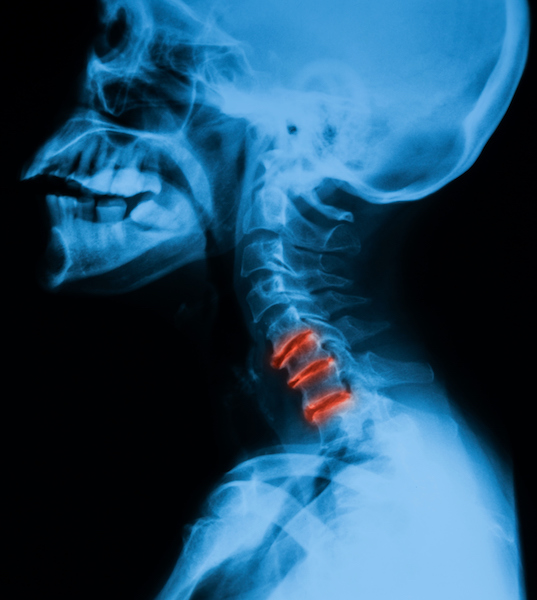

Chiropractors often use x-rays as part of the exam. X-rays of your neck can reveal if your discs between your spinal bones are wearing out or if you have some arthritis. If this happens, your nerves that come out of your neck and travel down your arm are more apt to get pinched.

In almost every case like this, there will be a loss of mobility and misalignments in the spinal bones of your neck. Chiropractors correct spinal misalignments by using chiropractic adjustments to help take the pressure off your nerves.